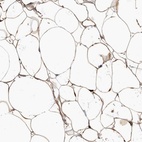

Immunohistochemical staining of human soft tissue shows cytoplasmic positivity in adipocytes.